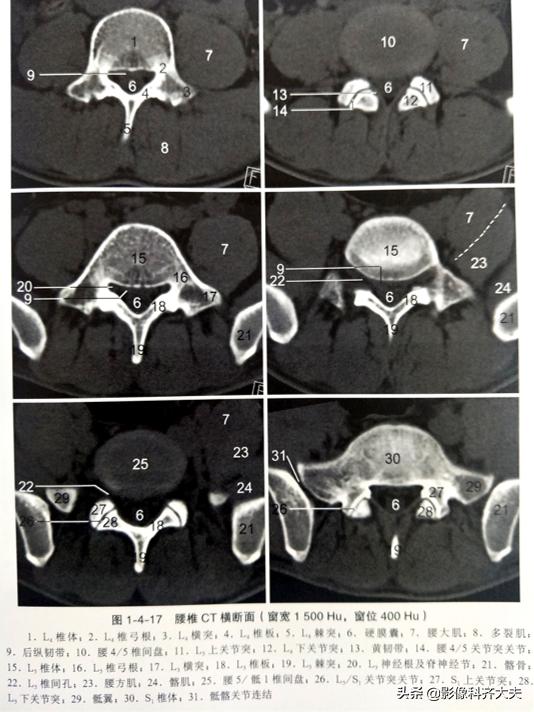

CT及MRI表现:

①正常腰椎间盘后缘不超过椎体骨性终板的后缘,且中部略有凹陷呈肾形。椎间盘脱出表现为局部突出于椎体后缘的弧形软组织影,通常与椎间盘相连,且密度多一致,并可见硬脊膜外游离髓核。髓核在椎间盘平面上方或下方,其密度低于椎骨但高于硬脊膜及椎旁软组织,突出的椎间盘可钙化。

②硬脊膜外脂肪受压、移位,甚至消失,硬脊膜下腔前缘或侧方受压变形。

③向侧后方突出的椎间盘,可使侧隐窝前、后径缩短,压迫相应的脊神经根使其向后移位;脊神经根亦可因水肿而增粗。

④椎体后部骨质硬化及有时可见椎间相邻椎体上、下缘可见许莫氏(Schmorl)结节。

椎间盘膨出CT及MRI表现:

①轻度膨出时表现为椎间盘后缘正常肾形凹陷消失,圆隆饱满。

②重度时弥漫膨出的间盘边缘明显向四周均匀一致增宽,超出上下椎体边缘,但椎间盘仍然对称,没有局部突出,外形保持椭圆形,可伴真空变性。严重时可造成硬膜囊受压狭窄,马尾神经受压。

CT椎间盘突出分型

以椎间盘疝出物突出的方向分为四型,即中央型、外侧型、远外侧型和侧前型。

前两种为椎管内型,后两种为椎管外型。

中央型椎间盘疝出物位于椎管中部主要对硬膜外脂肪间隙和硬膜囊形成压迫;

外侧型椎间盘疝出物位于椎管内一侧,未超过椎间孔内口,主要对硬膜外脂肪间隙、硬膜囊和神经根形成压迫;

远外侧型椎间盘疝出物位于椎管以外,主要引起椎间孔狭窄和一侧根神经受压;

侧前型椎间盘疝出物本身不引起压迫症状,但由于椎间盘的外1/3有神经分布,亦是腰痛的原因之一,所以应引起足够的重视。

椎间盘突出程度与椎管狭窄程度并不呈正比,椎管狭窄程度受疝出物大小、硬膜囊大小、韧带厚度、关节肥大和椎间盘膨出等因素的影响。